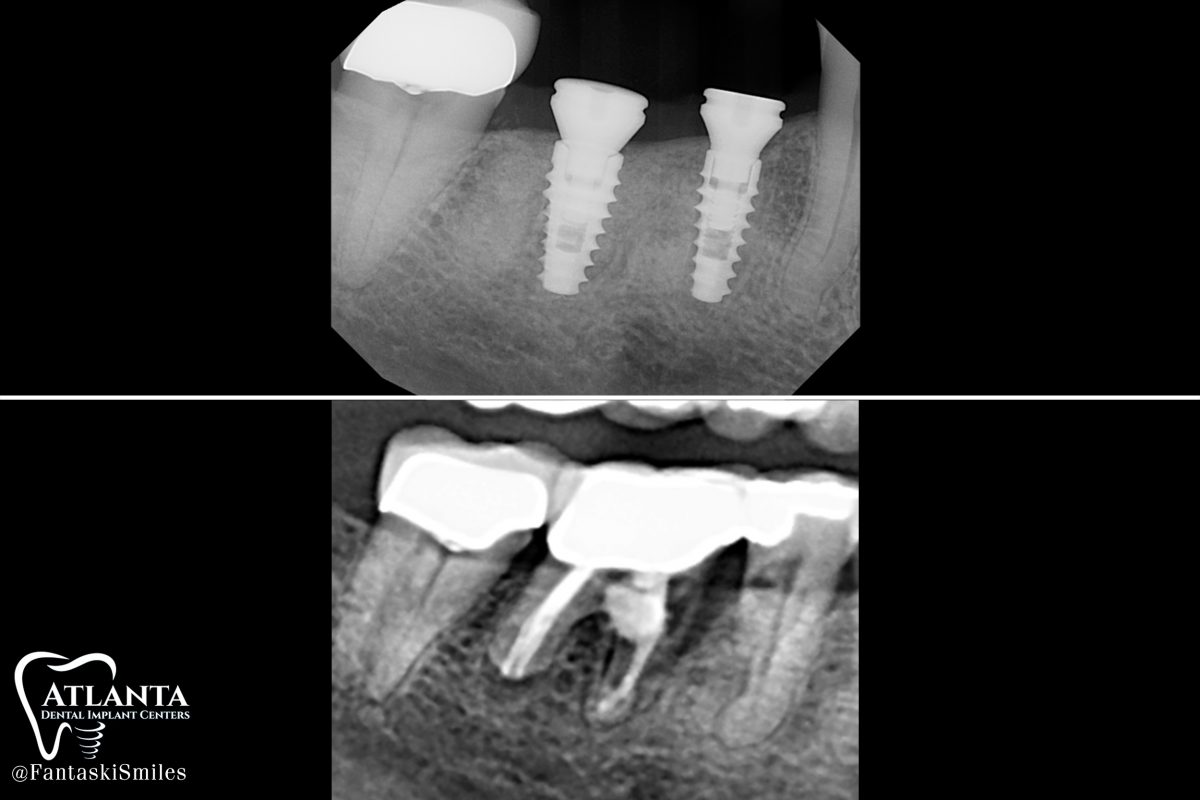

https://drfantaski.com/wp-content/uploads/2023/02/RB_Implant_xrays-1200x800.jpg